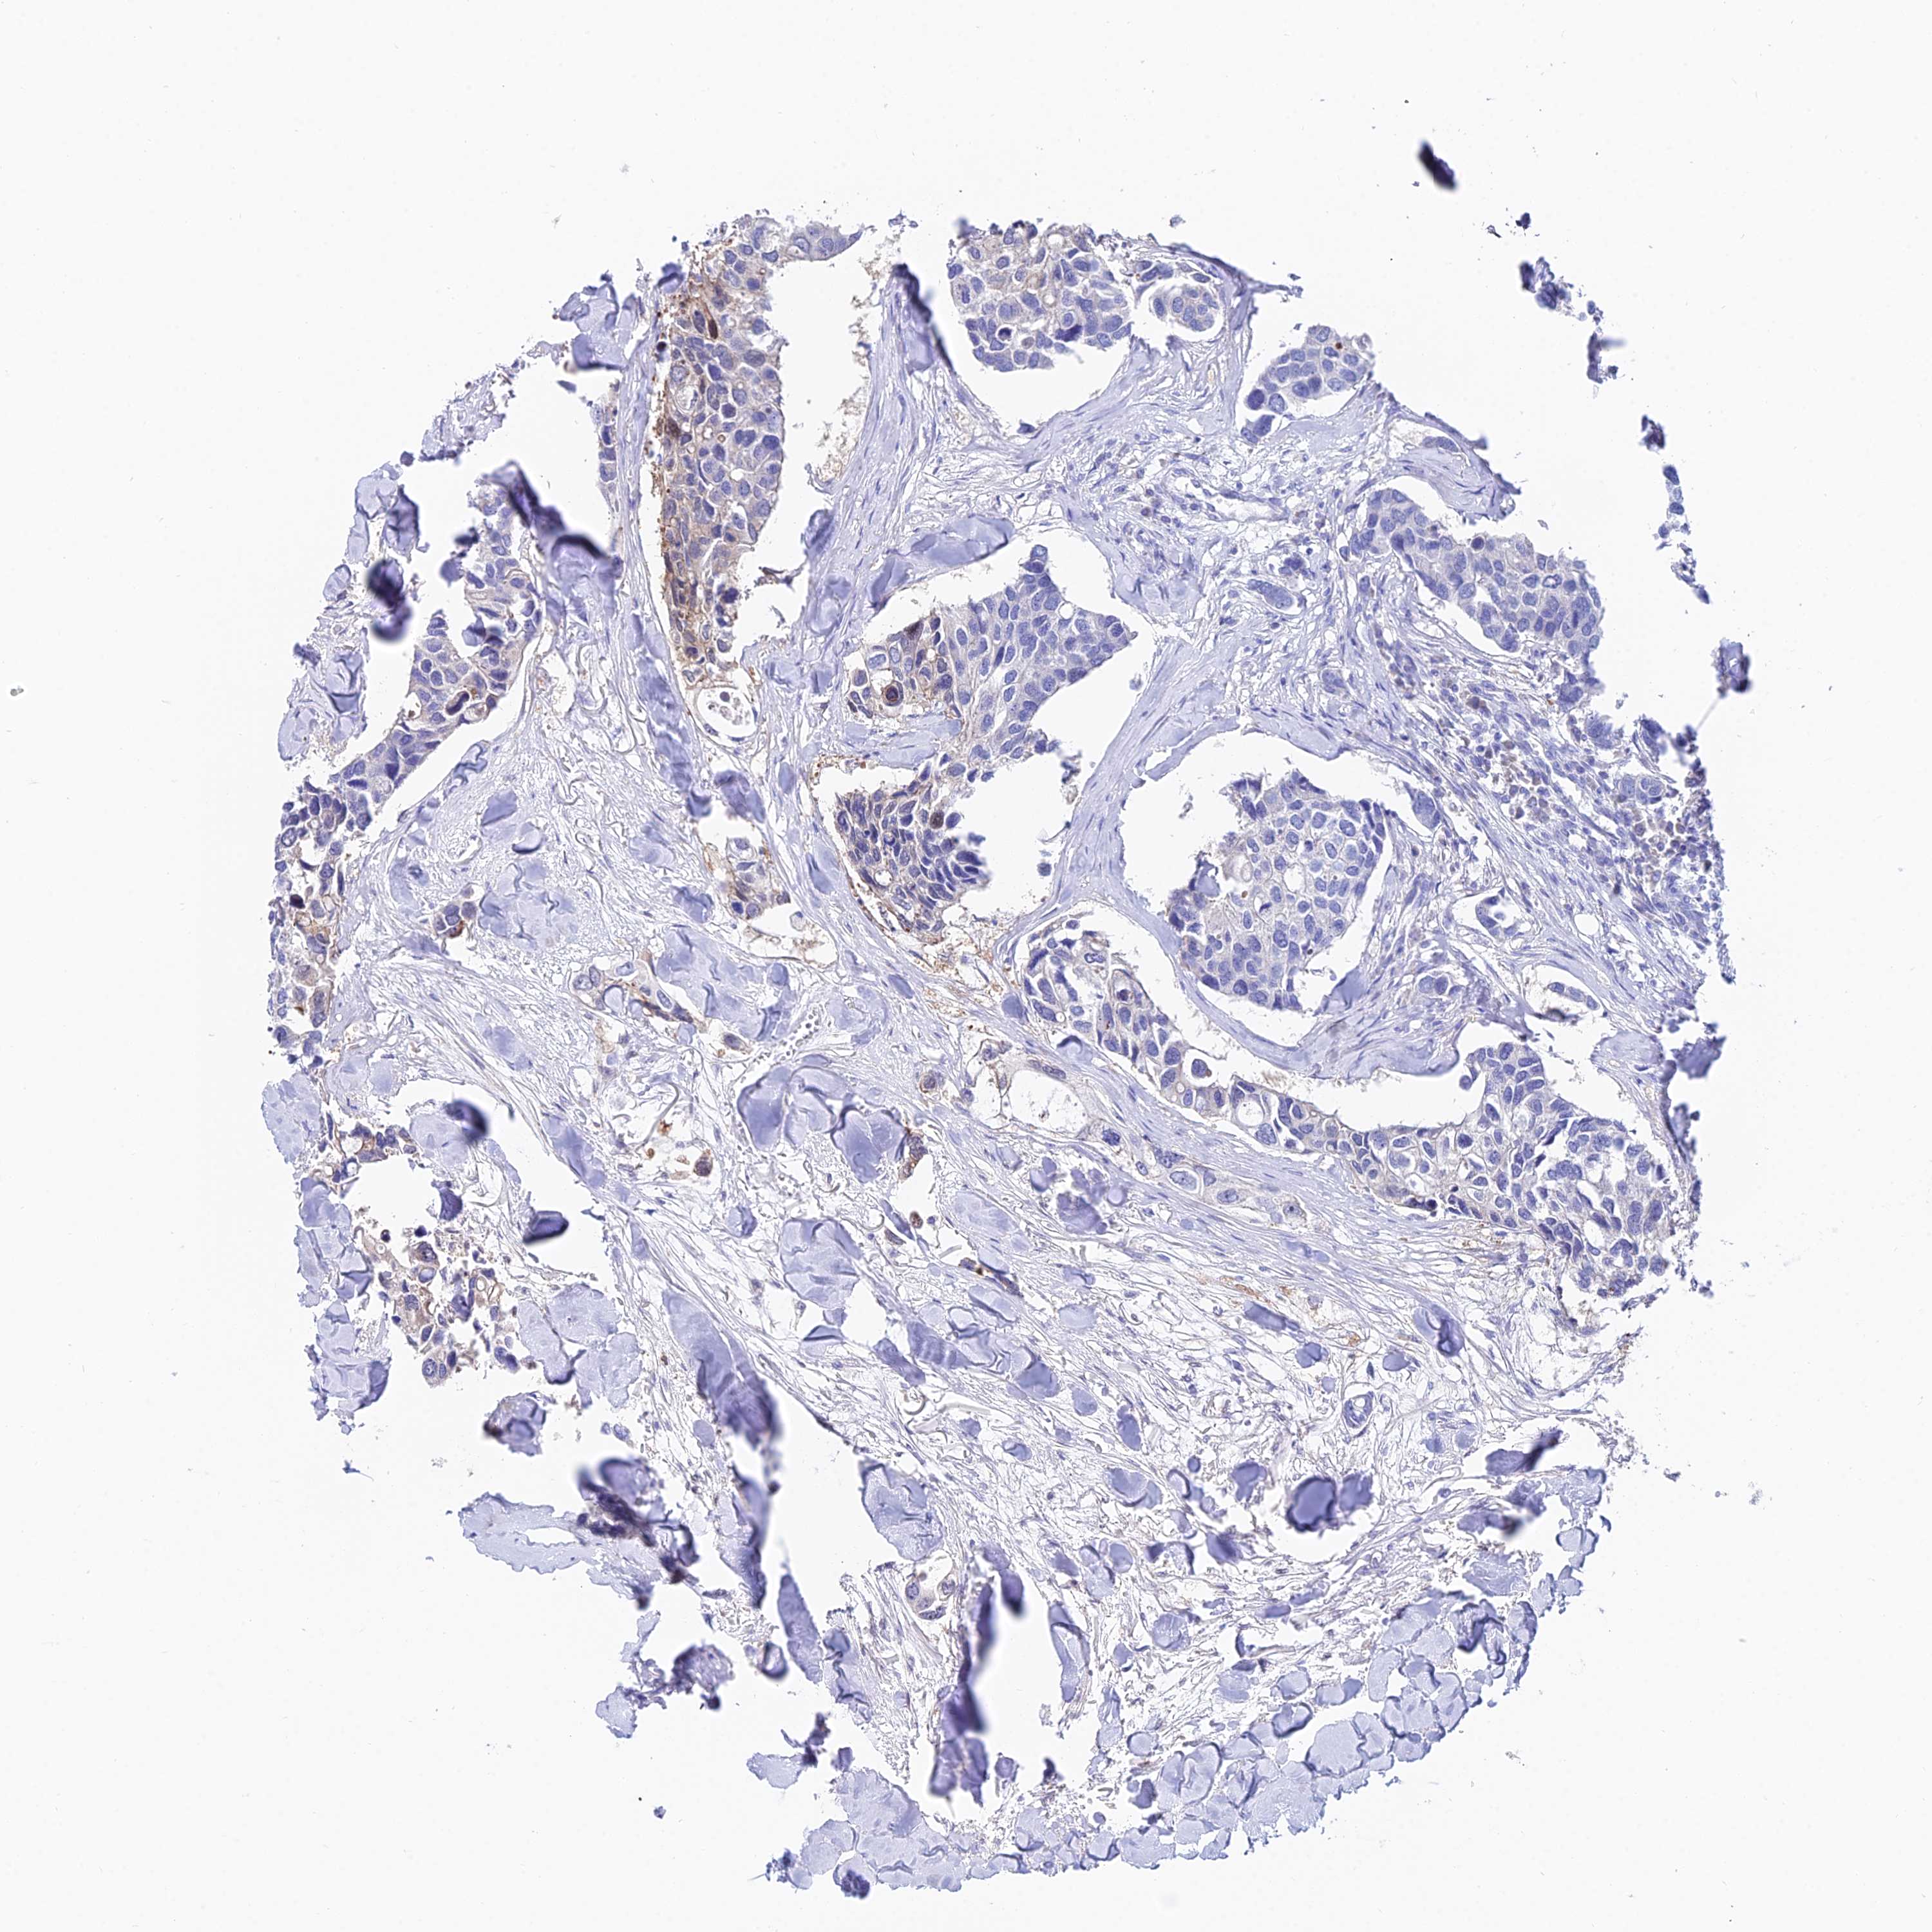

CANCER BREAST CANCER Show tissue menu

BRCA TCGA BRCA VALIDATION PROTEIN EXPRESSION

Breast cancer

Human cancer